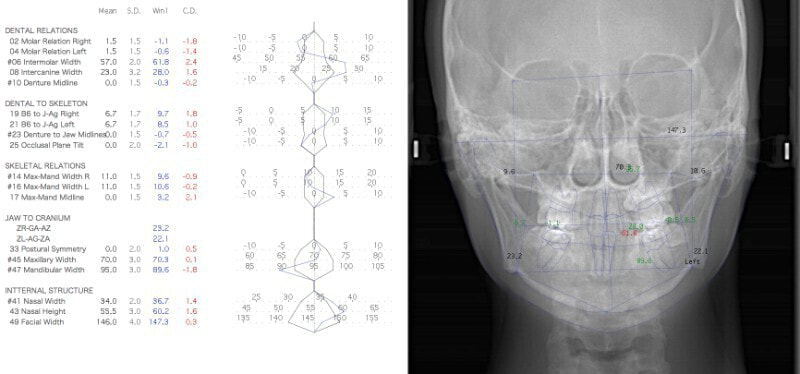

検査時のセファロ分析側貌

上顎劣成長の値が出ています。顔面、下顎骨骨体自体は標準偏差1S.D.内に収まっています。

顔面と顎骨の幅径はある程度確保されているので、非抜歯が可能であると診断しました。

治療後のセファロ分析です。

反対咬合の治療は、FX(フェイシャルアキシス)が開きやすいのですが、治療後も良好な値を保つことができました。FXがあまり開きすぎると、咬合力が落ちてしまいます。

下顎の右側への偏位は解消されました。

特に左側の咬合時の顎関節の位置に改善が認められます。